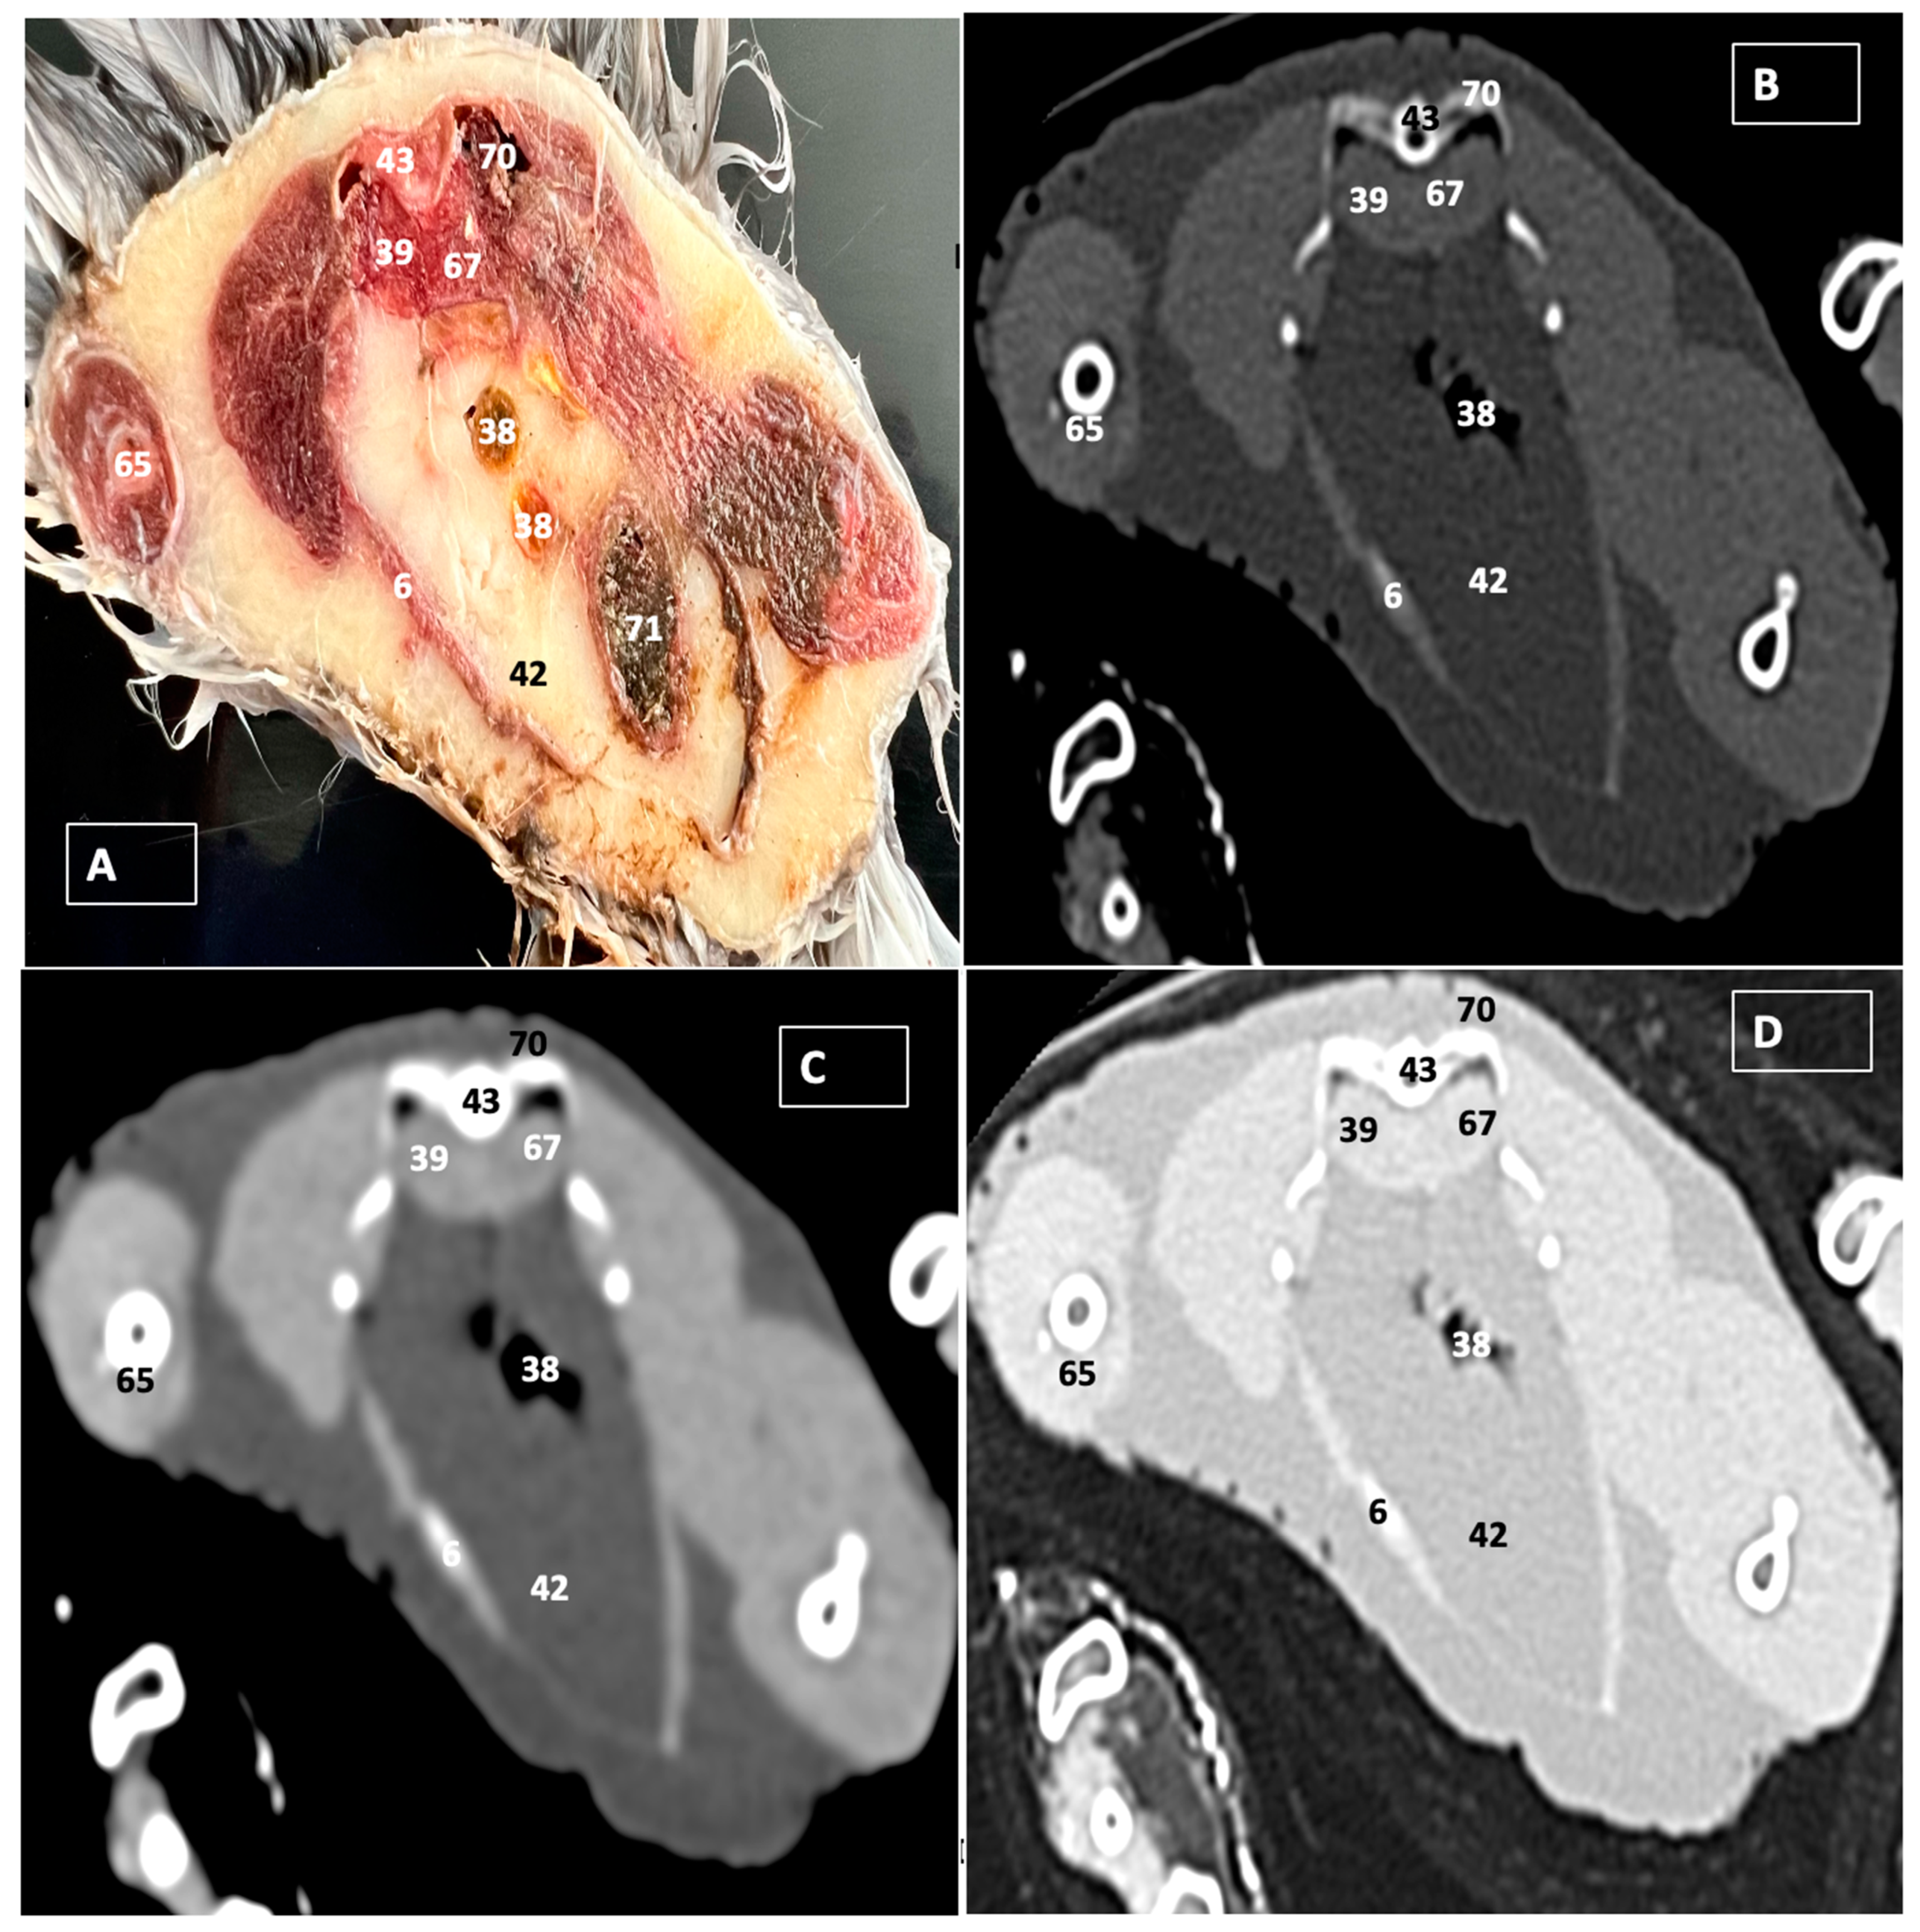

A Cadaveric Study Using Anatomical Cross-Section and Computed Tomography for the Coelomic Cavity in Juvenile Cory’s Shearwater (Aves, Procellariidae, Calonectris borealis)

3. Results

3.1. Anatomical Dissections and Cross-Sections

3.2. Computed Tomography Images